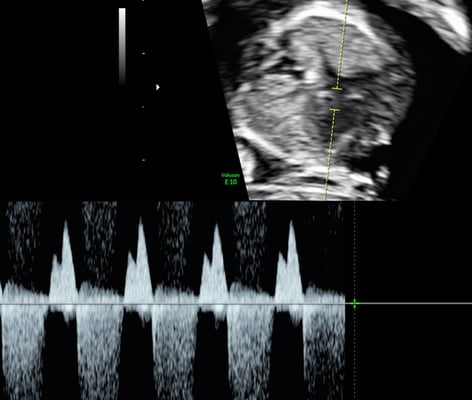

Im Rahmen des traditionellen Dopplersymposiums in Salzburg, welches heuer von 28. bis 30. April 2023 stattfindet, wird in diesem Jahr erstmals ein Fokustag in fetaler Echokardiographie am Samstag, 29. April 2023, angeboten.

Ziel dieser Veranstaltung ist es, innerhalb eines Tages einen umfassenden Einblick in das fetale Herz zu bekommen. Von der Embryologie zur sonographischen Darstellung der normalen Entwicklung, von der Genetik zur sonographischen Erkennung fetaler Herzfehlbildungen, von der Indikation für fetale Echokardiographie zur Indikation pränataler Intervention bei Vorliegen spezieller Herzfehler. Renommierte ExpertInnen mit langjähriger Erfahrung berichten aus ihrer täglichen Arbeit in Praxis- und Klinikalltag. Die KursteilnehmerInnen bekommen im Rahmen von Hands-on-Übungen die Möglichkeit unter Supervision die Standardeinstellungen der fetalen Echokardiographie an Schwangeren im 2. und 3. Trimenon zu erlernen.